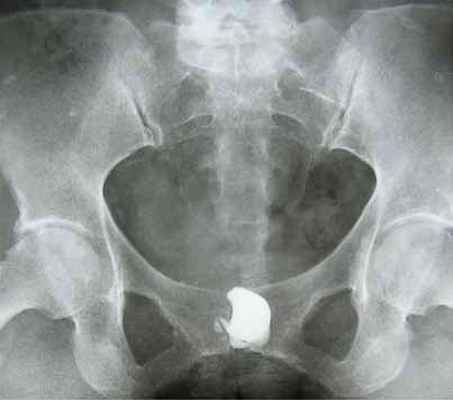

На экскреторной урограмме - анатомо-функциональных изменений со стороны почек, мочеточников и мочевого пузыря не выявлено. Выполнена восходящая уретроцистография, при которой визуализируется дивертикул уретры неправильной округлой формы диаметром до 4,5-5,0 см, дефектов контрастирования в проекции этого образования не обнаружено (рисунок 2).

После мочеиспускания определяется скопление контрастного вещества в дивертикуле уретры (рисунок 3).